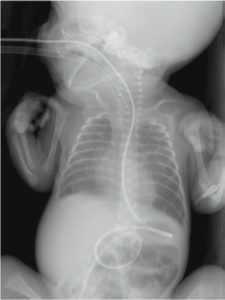

Рис. 5. Обзорная рентгенограмма грудной клетки и живота в прямой проекции. В питательный зонд введен рентгеноконтрастный препарат. На снимке видно, что конец зонда расположен за пределами привратника

Fig. 5. Plain radiograph of the chest and abdominal organs. An X-ray contrast agent was introduced into the tube. The image shows that the end of the probe is located outside the pylorus